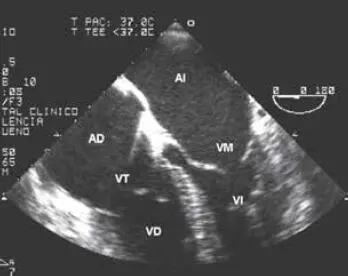

Fig 44 Proyección transversal de cuatro cámaras Abreviaturas AD aurícula - фото 43

Fig. 4.4 Proyección transversal de cuatro cámaras. Abreviaturas: AD = aurícula derecha; AI = aurícula izquierda; VD = ventrículo derecho; VI = ventrículo izquierdo; VM = válvula mitral; VT = válvula tricúspide.